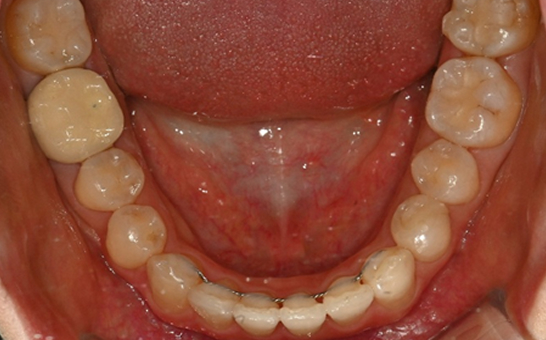

바른선택치과의원에서 사용하는 아이테로는 인비절라인치료를 위한 디지털 구강 스캐너로,

기존의 불편한 치아 본뜨기(인상 채득) 없이 3D 디지털 스캔으로 빠르고 정밀한 치아 상태 분석이 가능합니다.

기존의 물리적 본뜨기(알지네이트/실리콘 인상)보다

정확도가 높고, 환자의 불편함이 적습니다.

실시간 3D 데이터 분석을 통해 교정 전/후의

예상 결과를 시각적으로 빠르게 확인이 가능합니다.

단순히 치아 배열만 보는 것이 아니라, 교합 상태, 치아 마모,

교정 필요성까지 정밀 분석이 가능합니다.

치아와 교합 상태를 정밀하게 분석하여

환자에게 맞는 인비절라인 치료 설계가 가능합니다.

오차범위와 불필요한 체득과정을 줄여 빠르고, 정밀하게 스캔 가능한 인비절라인 전용 아이테로 스캔